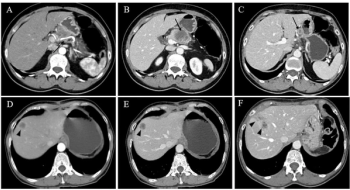

In comparison to a model based on clinicopathological risk factors, a CT radiomics-based machine learning model offered greater than a 10 percent higher AUC for predicting five-year recurrence-free survival in patients with non-metastatic clear cell renal cell carcinoma (ccRCC).